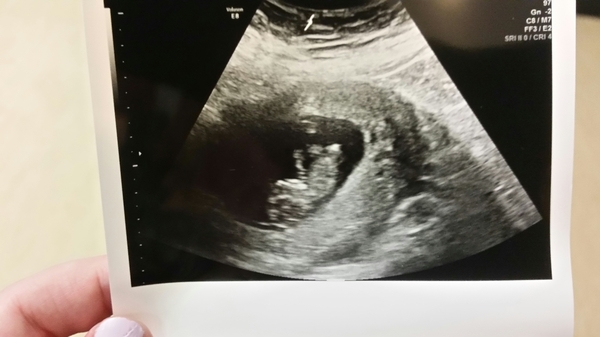

I don't know if it will be too late for the tests but I've taken the appointment. Partly because my best friend is convinced im having twins, my scan photo from 10+5 has what is probably shading but she thinks it's a second sac behind the main one in the photo with the image of a second baby's head, body and arm. I can't stop looking at the photo so I'm going to get them to have a good look around. Can you see what I'm taking about in the bottom right of the pic?

oddsocks it looks beyond the uterine wall to me but very much a lay person reading it.

Thanks @mummyagainmaybe I'm pretty sure you're right. I laughed it off at first but I think it's part of the terror/fun of pregnancy, that you really have no idea what's going on in there and imagine all sorts. It has definitely taken some of the fear out of the first trimester having something funny to think about